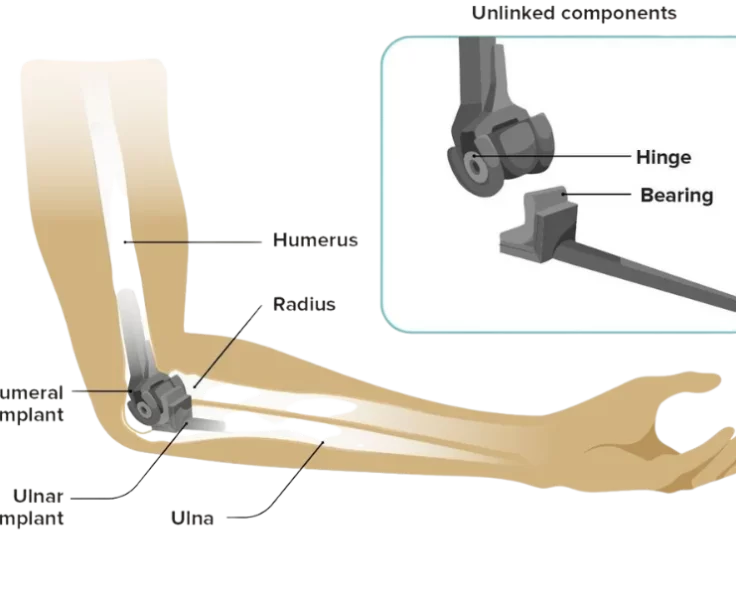

Total Elbow Replacement

The elbow is an essential joint for regular everyday functioning, but it is susceptible to a variety of degenerative disorders as well as traumatic lesions…